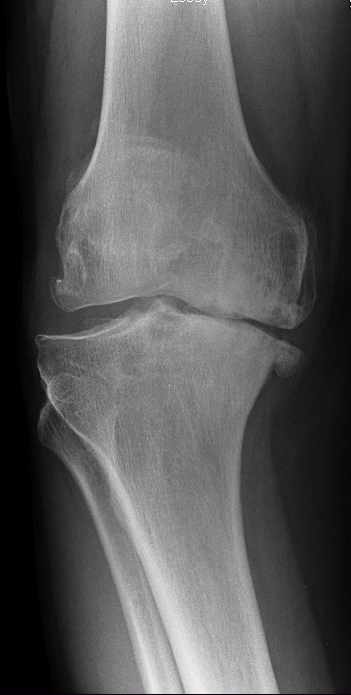

In knee OA, the protective cartilage that covers the ends of the bones within the knee joint gradually deteriorates, leading to friction, inflammation, and damage to the underlying bone. This results in pain, stiffness, swelling, and reduced range of motion in the affected knee. As the disease progresses, bone spurs (osteophytes) may develop, further contributing to joint pain and dysfunction.

The diagnosis of knee OA is typically based on a combination of clinical evaluation, medical history, physical examination findings, and imaging studies such as X-rays or MRI scans.